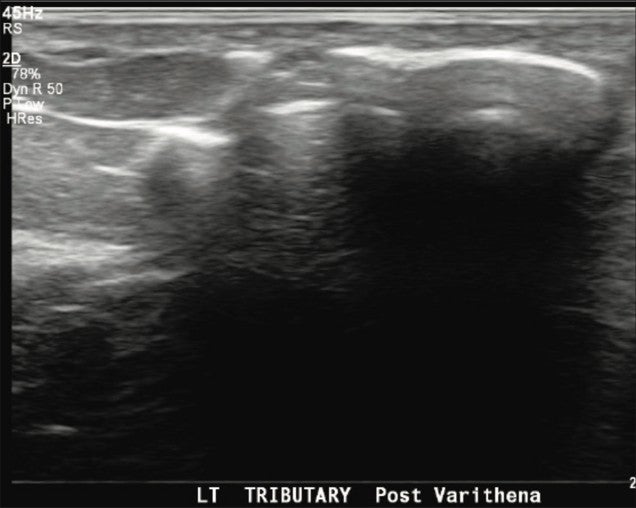

Immediately after the procedure, successful venospasm of the treated varicosities and residual GSV were documented with duplex and grayscale imaging. A final ultrasound image was obtained to confirm a patent and compressible left common femoral vein Saphenofemoral Junction (SFJ).

Figure 3. Left GSV tributary vein immediately post Varithena treatment.